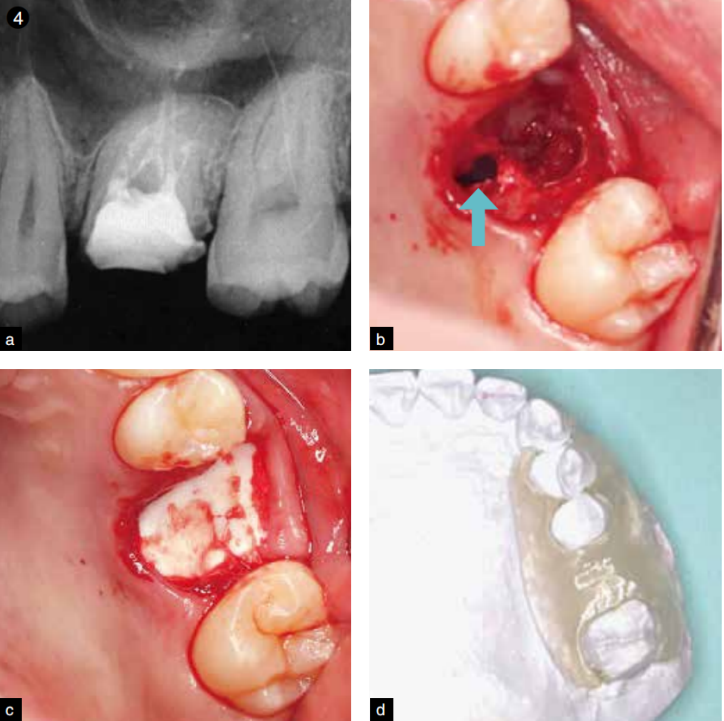

图4 a为拔牙前的牙片;b为腭侧根穿孔;c为填入胶原塞(缝合前);d为制作保护板